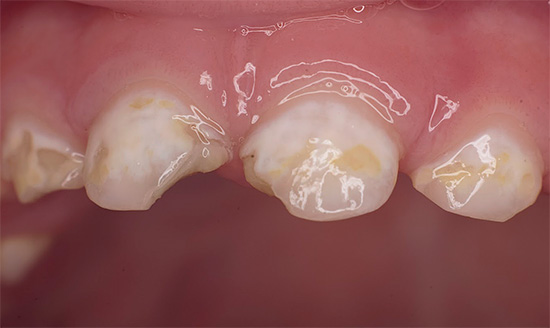

Oggi, a causa della popolarità della cura orale e della disponibilità di servizi dentali, la malattia è diventata meno comune, ma il problema è ancora rilevante nelle aree rurali e nei bambini in età scolare, quando quasi tutti i denti di un bambino sono affetti da carie (vedi l'esempio nella foto), e i genitori non sanno cosa fare in una situazione del genere.

Oltre al fatto che la carie è pericolosa per la salute, provoca dolore e limita la scelta del cibo, è anche un grave problema estetico. La foto sotto mostra un esempio di carie generalizzata:

La foto sotto mostra un altro esempio di corsa carie dei denti decidui in un bambino: